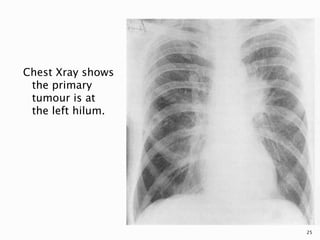

 Central tumours may be visible on the chest

density in the hilar region.

Chest Xray shows

the primary

tumour is at

the left hilum.

25